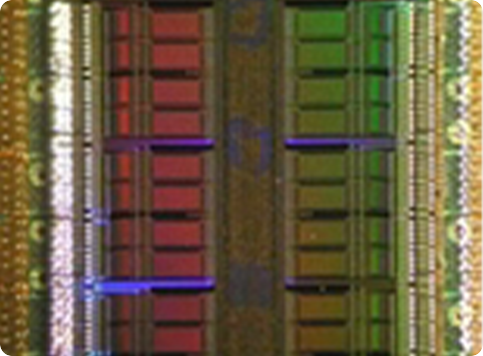

Our Avalanche Photodiode (APD) based technology for PET was developed by a R&D Consortium including PETsys S.A., with a focus on research and development. The R&D Consortium licensed this technology to PETsys SA. The APD-based photon detectors use matrices of LYSO scintillation crystals coupled to APD arrays. The APD signals are readout and sampled by a dedicated ASIC with 192 channels.

Several crystal-APD units and the corresponding frontend electronics are assembled in detector modules. Our APD-based detector module has 384 LYSO 2x2x20 mm crystals and covers a detection area of ~4x8 cm. One of the advantages the APDs is the capability of performing the double readout of the scintillation crystals, which allows to calculate the DoI of the detected photons. Associated to the fine detector pitch (2x2 mm) and the one-to-one coupling between crystal and APD pixels, the DoI capability permits an excellent spatial resolution of the order of 1.3 mm over the whole Filed-of-View.